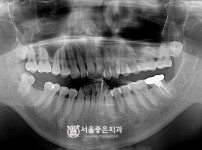

뼈이식 수면 임플란트 1개 - 오스템 임플란트 / 흔들림 심하여 발치 후 임플란트

해당 게시물은 의료법 제56조에 의거하여 로그인 후 열람이 가능합니다.

구분 임플란트